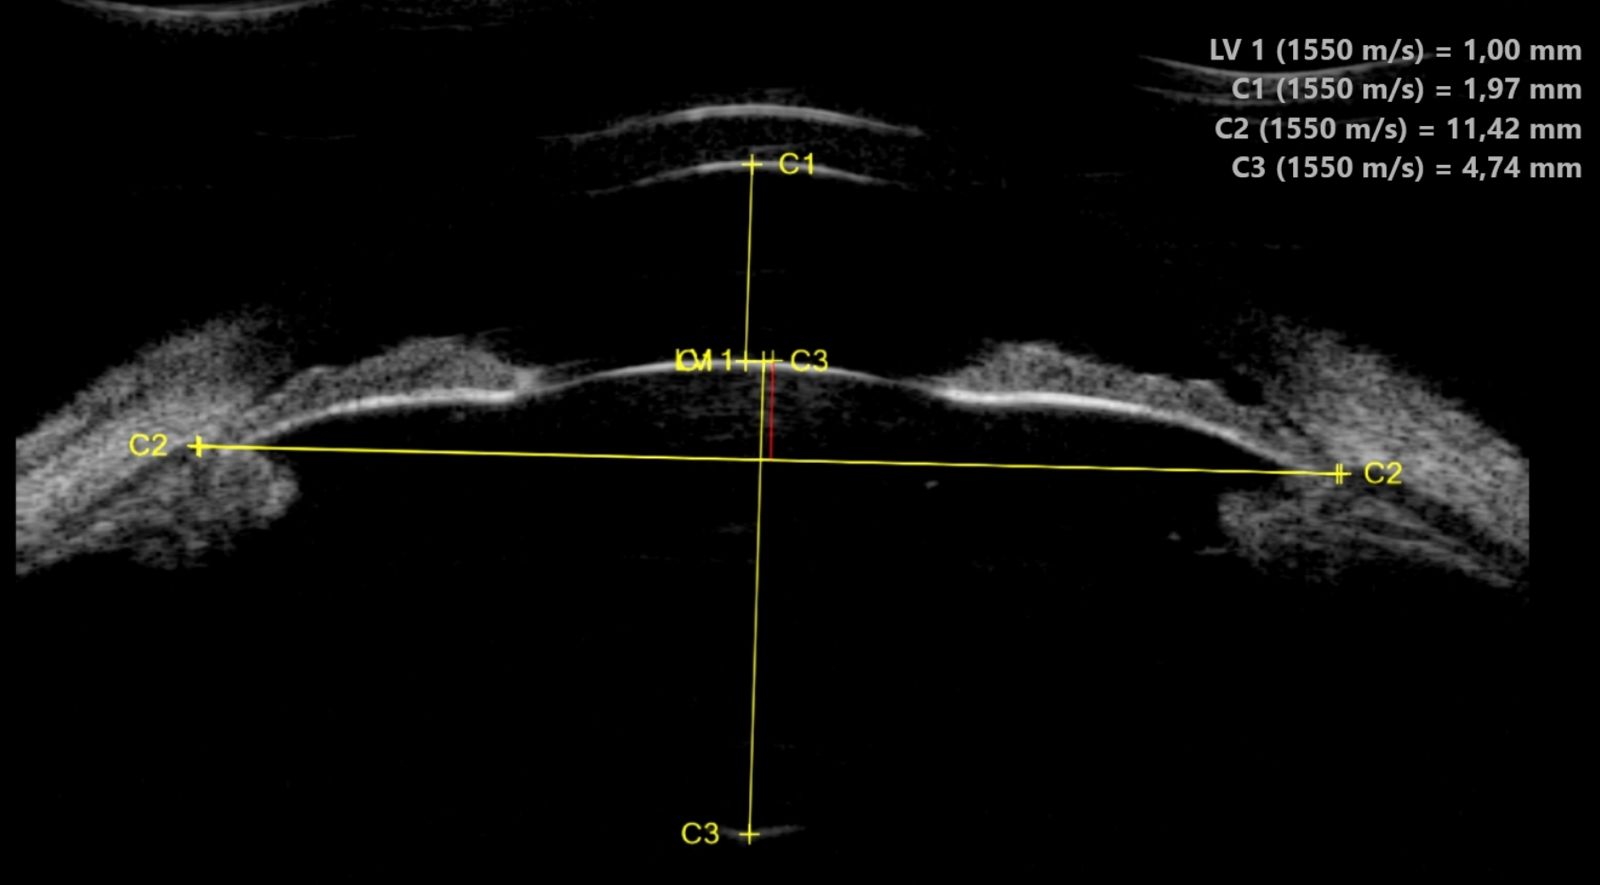

Corps ciliaire et sulcus

L'UBM est la seule technique d'imagerie permettant de visualiser le corps ciliaire dans sa totalité : processus ciliaires, pars plana, zonules. Elle mesure le sulcus ciliaire (diamètre sulcus-à-sulcus), donnée indispensable pour le dimensionnement des implants phakes ICL (Implantable Collamer Lens). Un mauvais dimensionnement peut entraîner un glaucome par contact iris-implant ou une cataracte par contact cristallin-implant.

Implants et chirurgie

L'UBM contrôle le positionnement des implants intraoculaires : implants de chambre postérieure (vaulting de l'ICL par rapport au cristallin), implants de chambre antérieure (distance par rapport à l'endothélium cornéen), implants suturés à la sclère. Elle évalue également les complications post-opératoires : déplacement d'implant, synéchies antérieures, fibrose capsulaire.

UBM du segment antérieur — Anatomie haute résolution UBM — Biomicroscopie ultrasonore du segment antérieur Anatomie du segment antérieur Chambre antérieure Cornée Épithélium + stroma + endothélium Iris Corps ciliaire + processus ciliaires Cristallin Angle Diamètre sulcus-à-sulcus (mesure ICL) 50 MHz Image UBM résultante Cornée Chambre antérieure Iris Iris Cristallin CC CC Angle 1 mm Avantages de l'UBM Visualise derrière l'iris (impossible en OCT) | Résolution 25-50 µm | Mesure du sulcus pour ICL

Biomicroscopie ultrasonore (UBM) à 50 MHz : l'anatomie du segment antérieur (à gauche) est reproduite avec une résolution exceptionnelle sur l'image UBM (à droite). L'angle irido-cornéen, le corps ciliaire (CC) et le sulcus sont visibles en détail, permettant le diagnostic du glaucome par fermeture de l'angle et le dimensionnement des implants phakes.